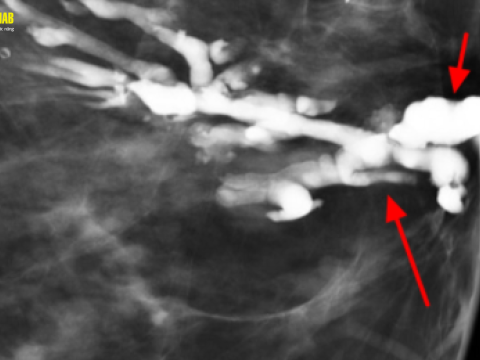

Điều trị viêm tắc tia sữa